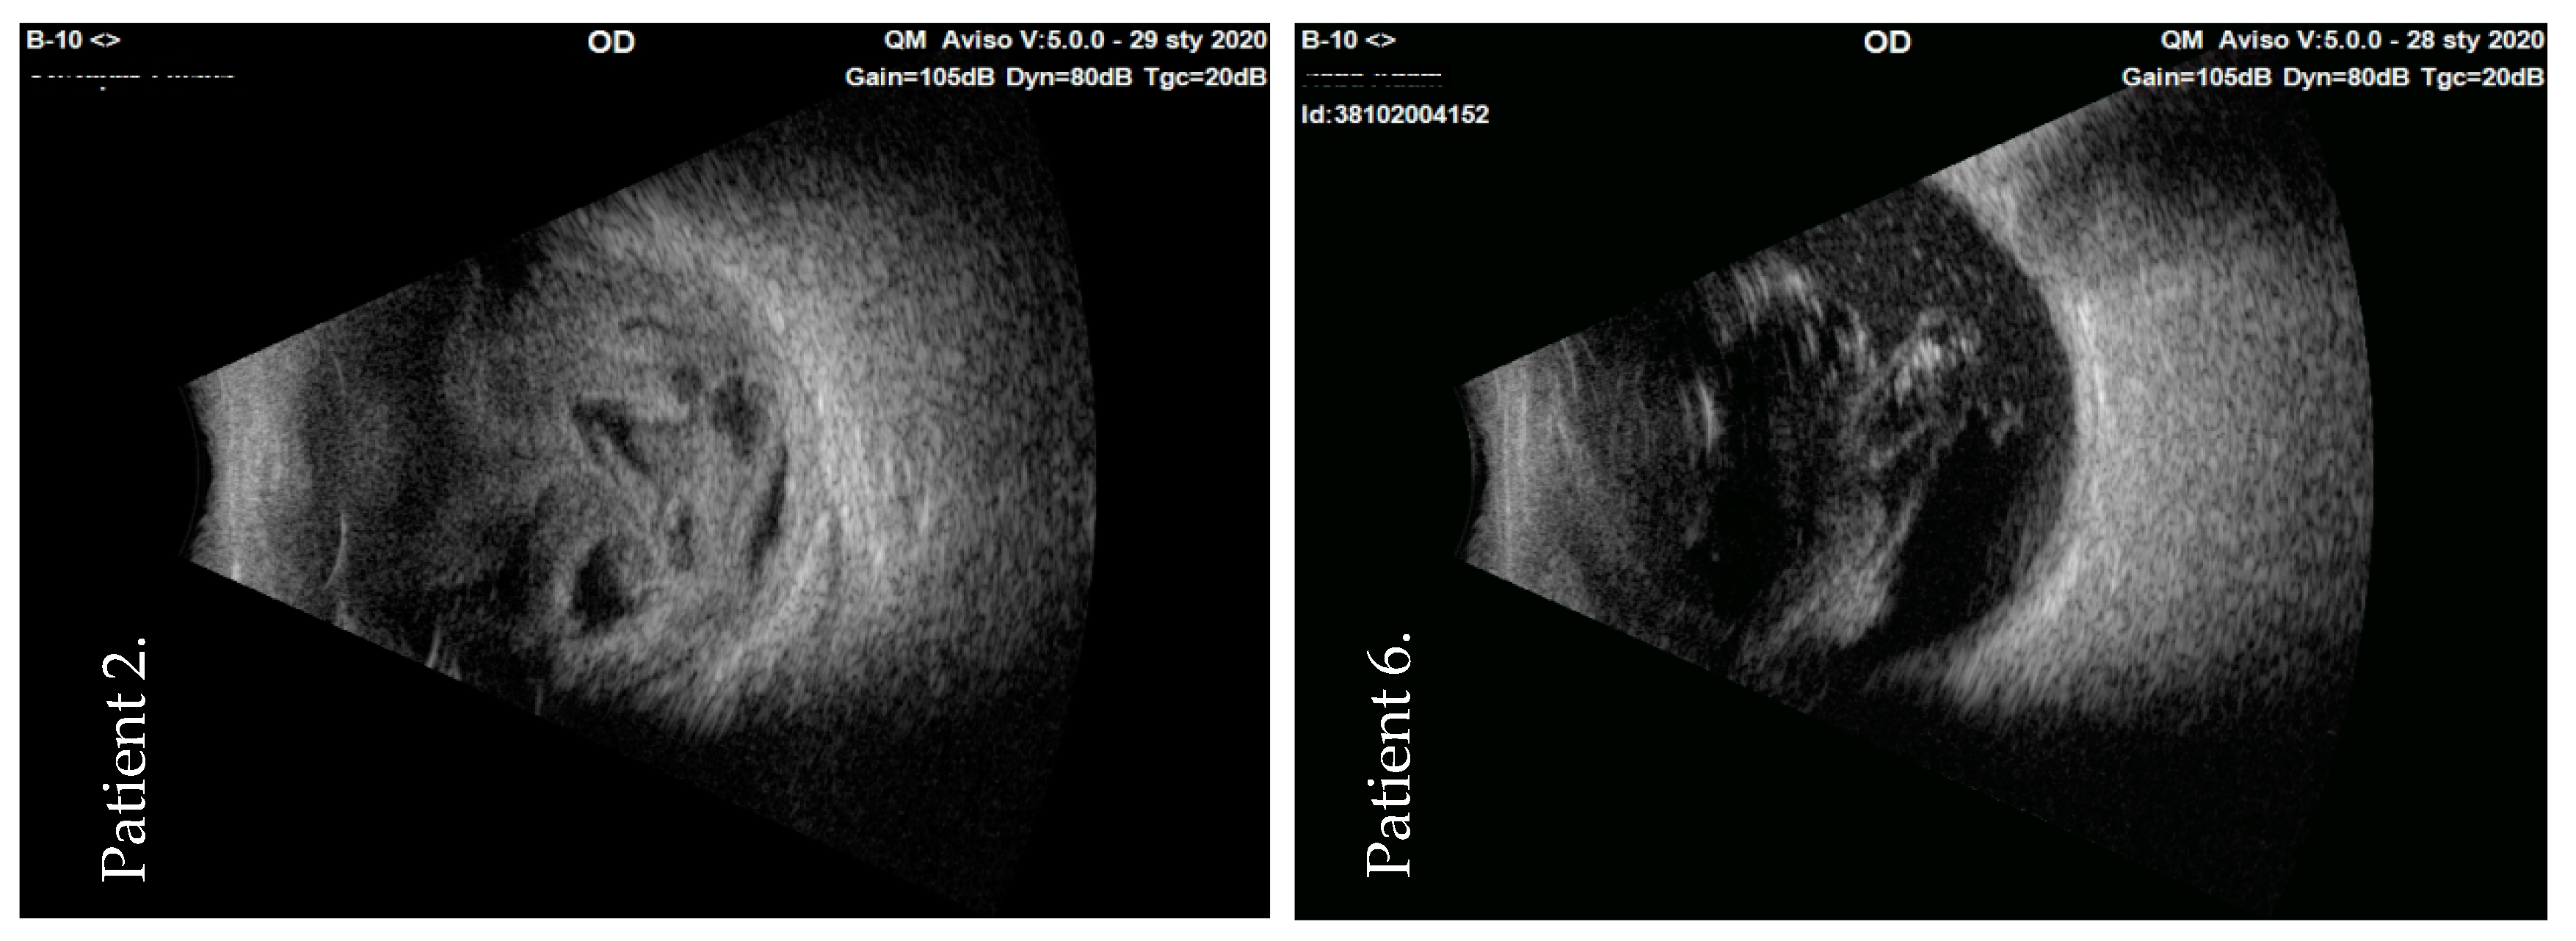

| 2 | M | 82 | Streptococcus mitis/oralis | 1. PPV + vancomycin + anterior chamber rinsing + BSS tamponade 2. PPV + vancomycin + abrasion + anterior chamber rinsing + silicone oil tamponade | NLP | HM | PCO | Attached | ||